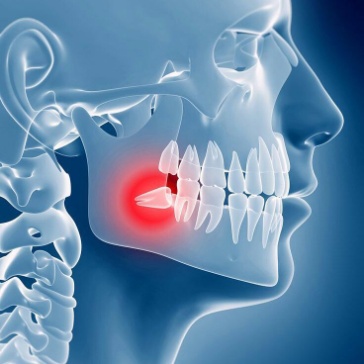

Estrazione elementi dentari inclusi/disodontiasi

Non sempre la chirurgia orale , preposta alla estrazione del terzo molare(o dente del giudizio) è tecnicamente di facile esecuzione e puo' essere praticata in un convenzionale ambuatorio odontoiatrico perchè la difficoltà di estrazione chirurgica è in rapporto sia alla posizione del dente ritenuto nell'osso ma anche in rapporto alla vicinanza con il canale contenente il nervo mandibolare.

Nei nostri nosocomi viene attentamente valutato caso per caso e dopo attento e scrupoloso approfondimento diagnostico (OPT - TC - TC Cone Beam), a seconda della complessità estrattiva , organizzata la seduta operatoria che puo' essere eseguita ambulatorialmente in regime di day surgery(il paziente viene ricoverato al mattino e dimesso il giorno stesso) o nei casi piu' complessi in sala operatoria con anestesia generale e supporto anestesiologico.